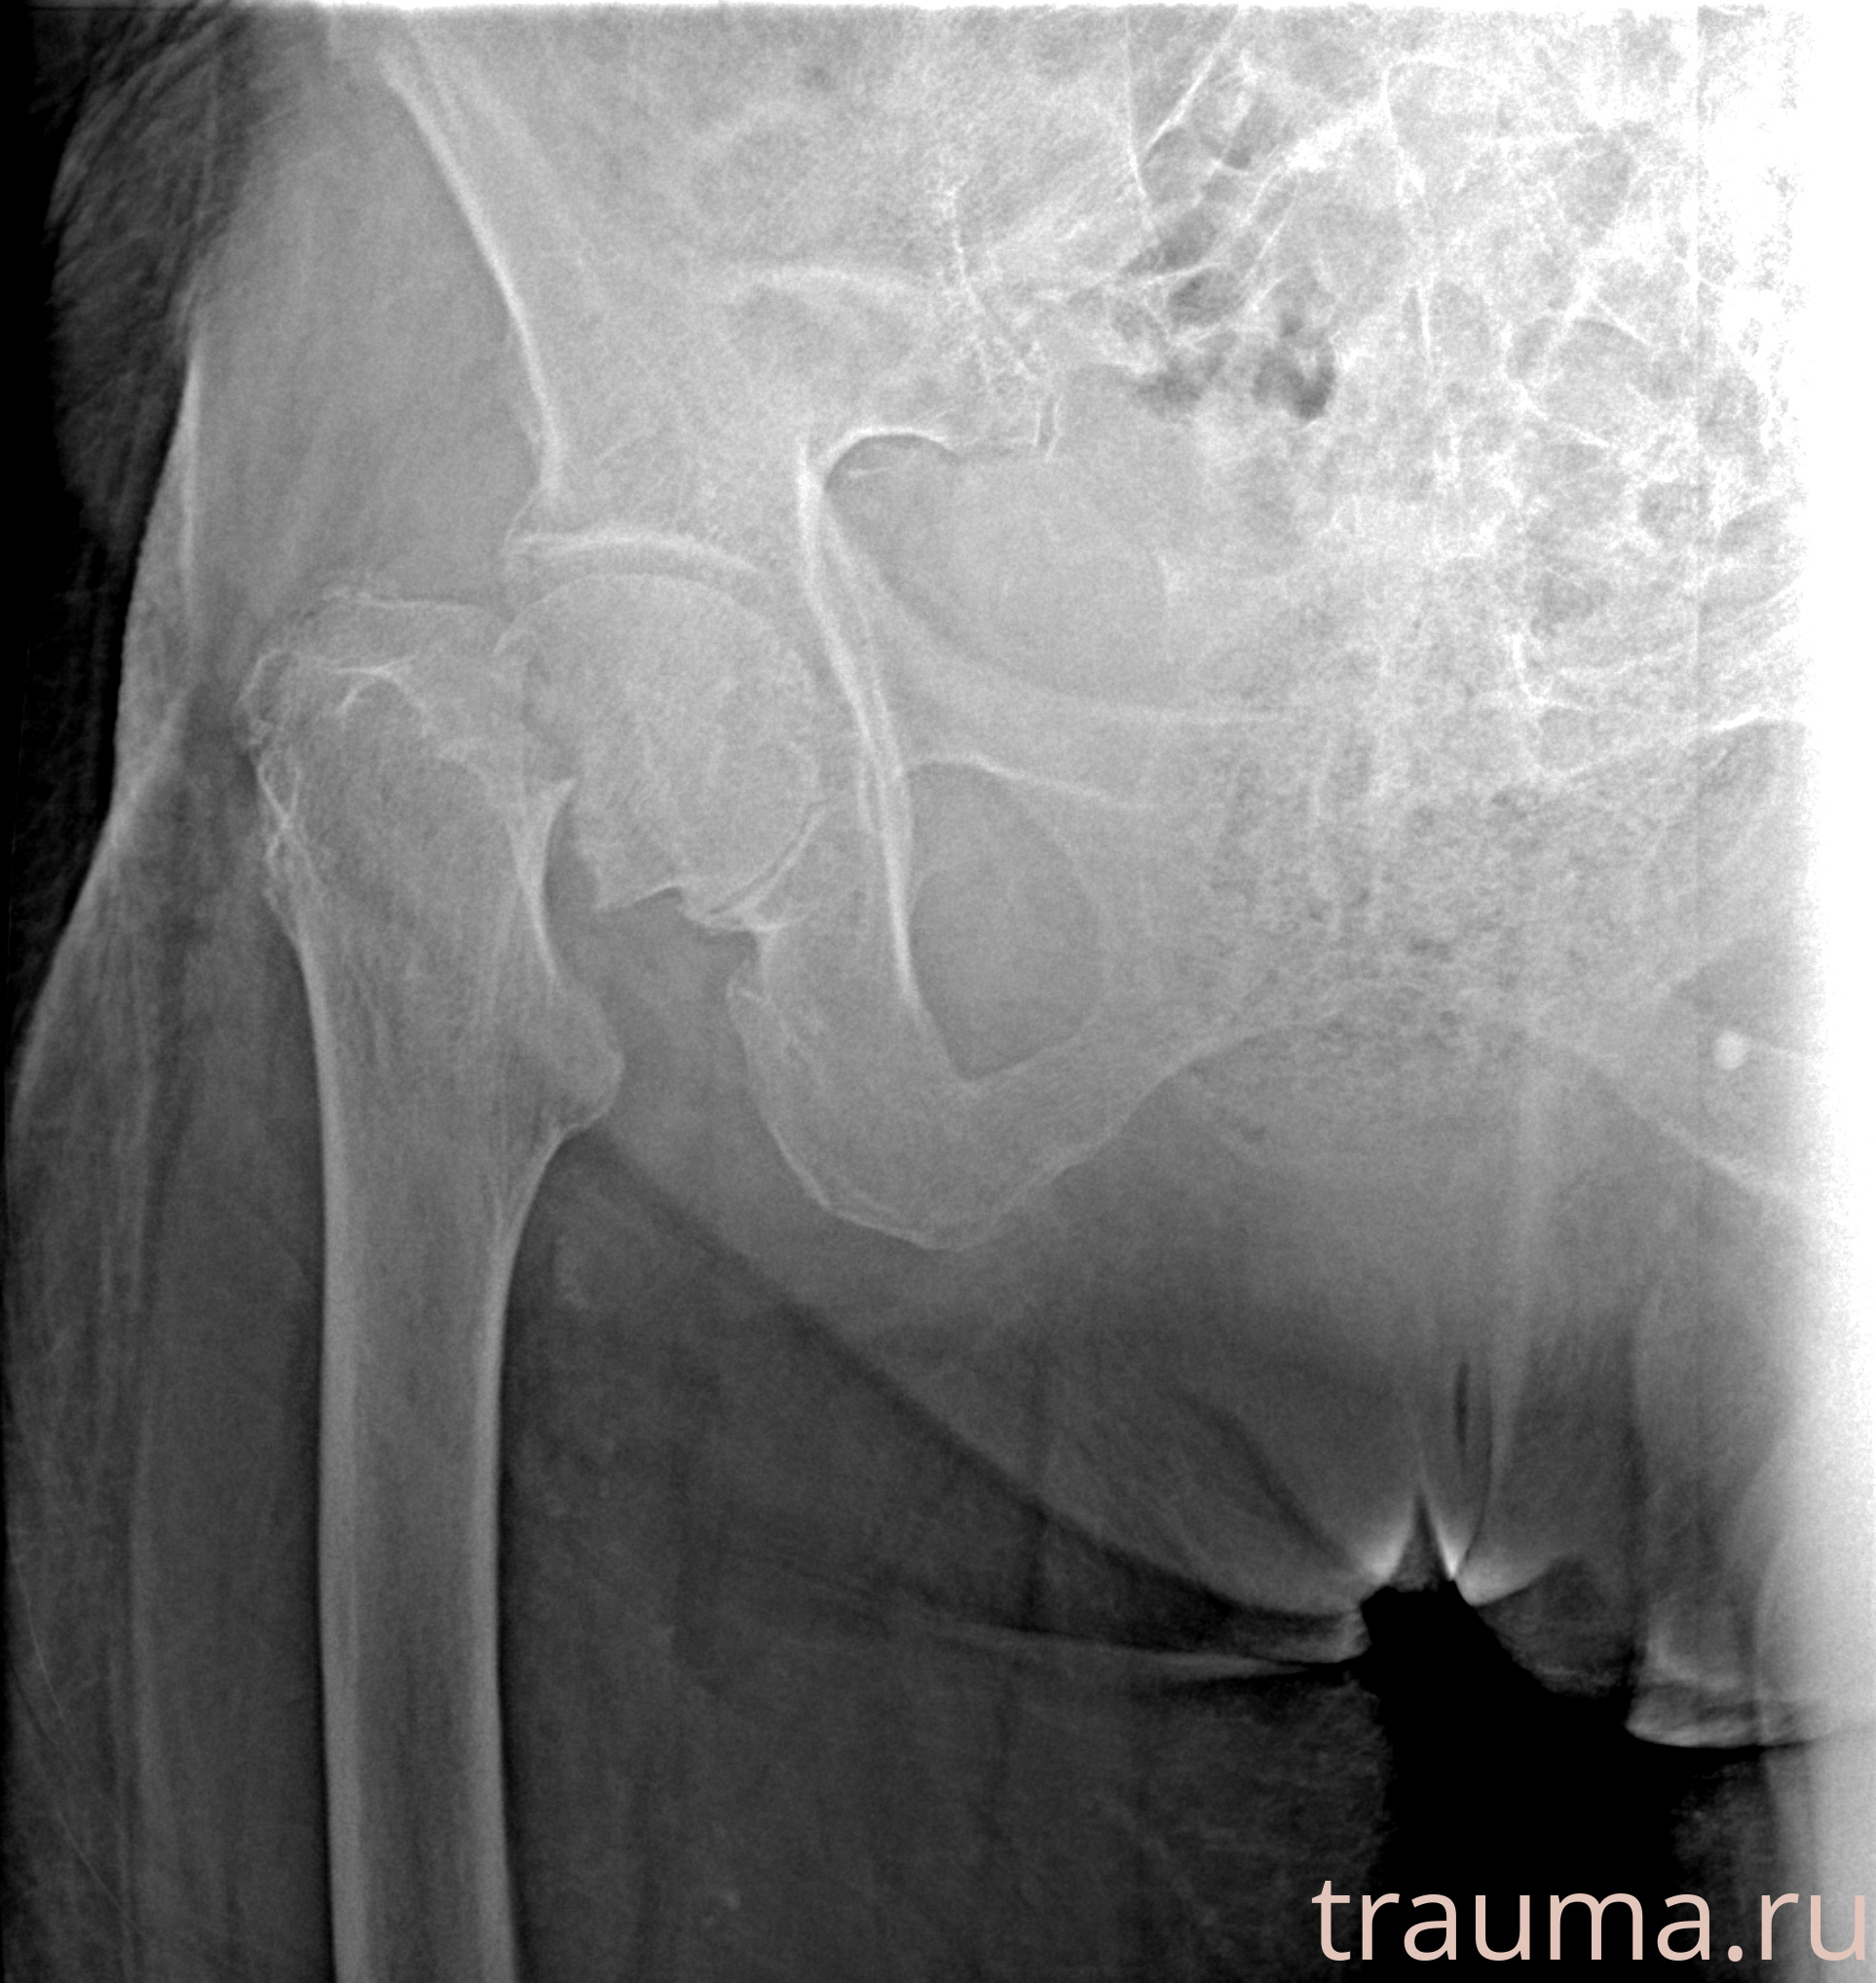

Рентгенограммы

Рентген на дому: по вашему адресу приезжает врач-рентгенолог, травматолог-ортопед с мобильным рентгеновским аппаратом, проводит диагностику травмы или заболевания, делает необходимые рентгенограммы, дает рекомендации по дальнейшему лечению. Получить качественные снимки в домашних условиях возможно благодаря уникальной методике, разработанной МосРентген Центром для института  Склифосовского